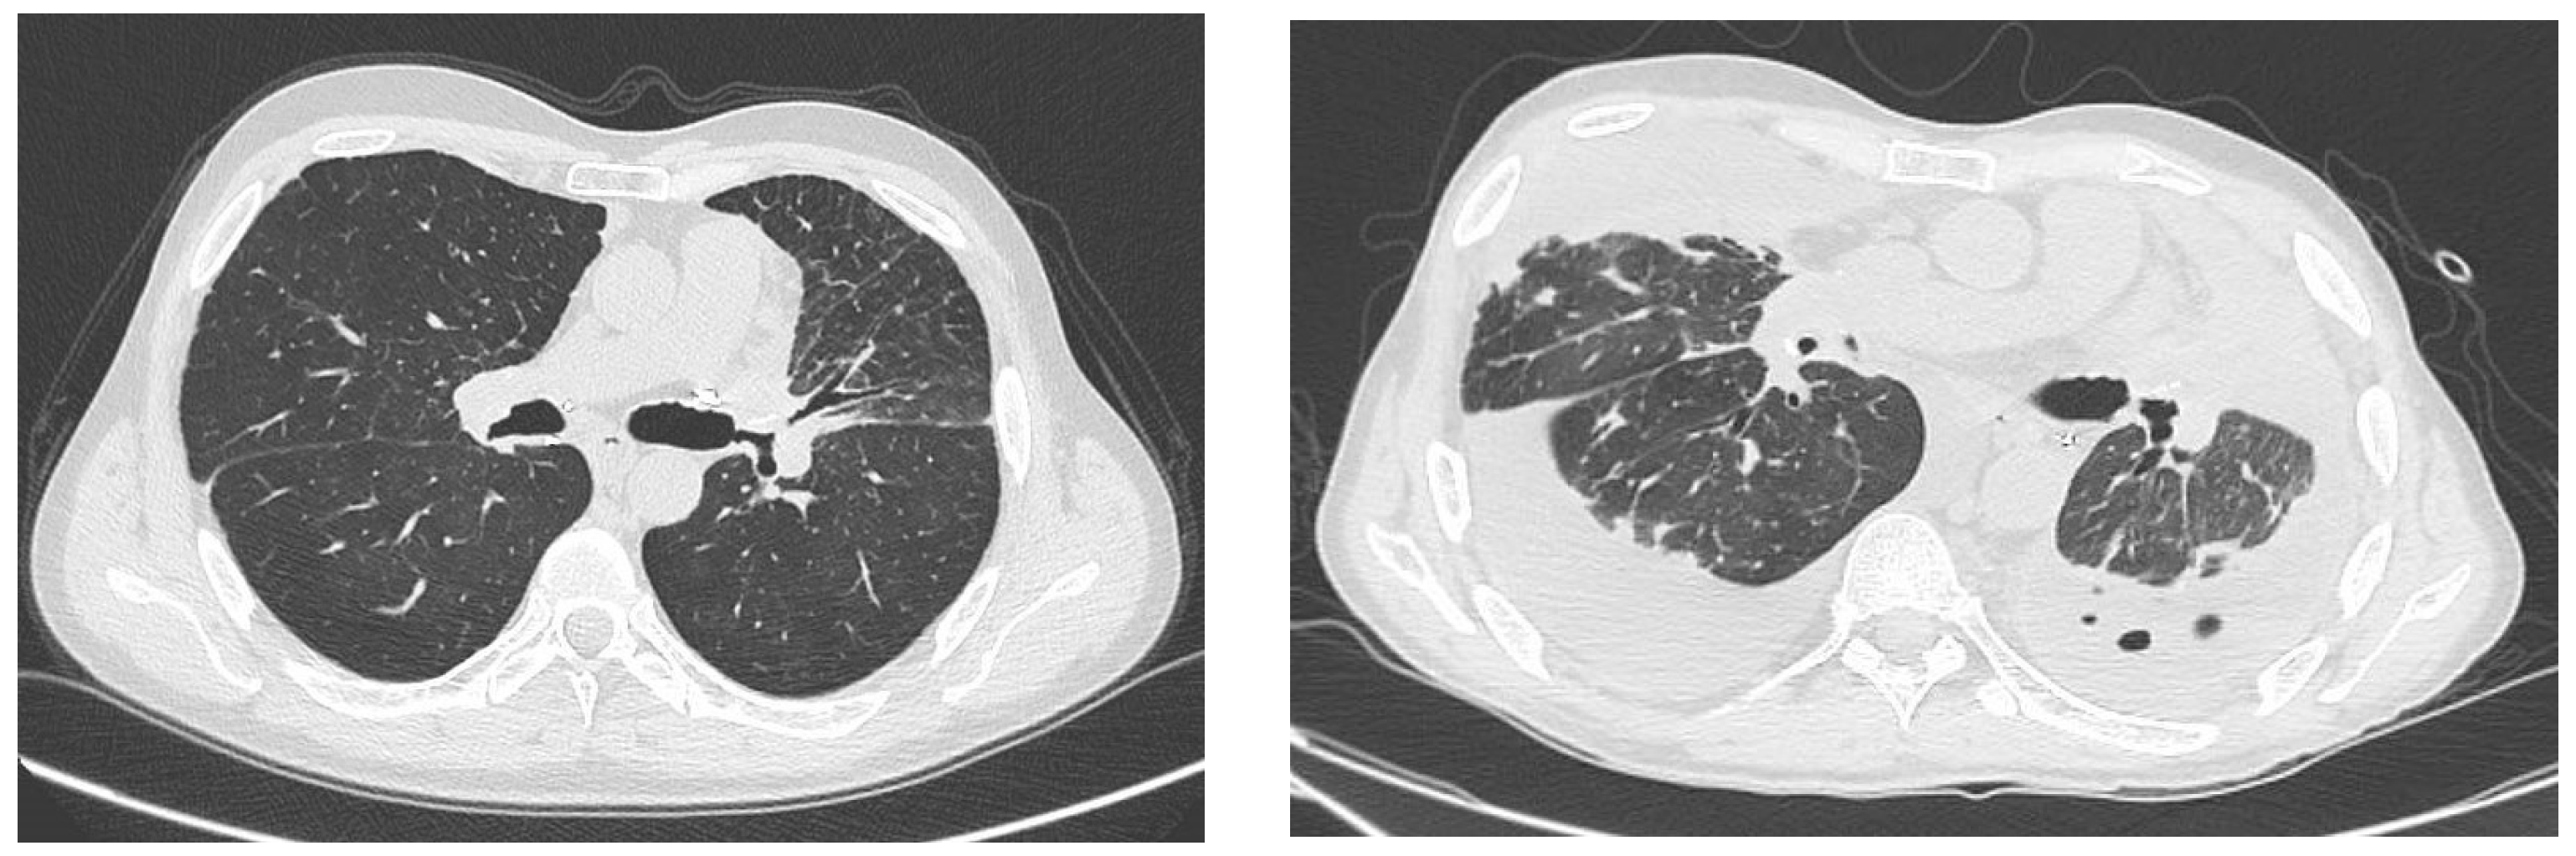

2. Case #1

Figure 1. Case #1. Chest CT in December 2022 (left) and January 2023 (right). In January 2023, we observed an increased lung parenchymal involvement compared with December 2022.